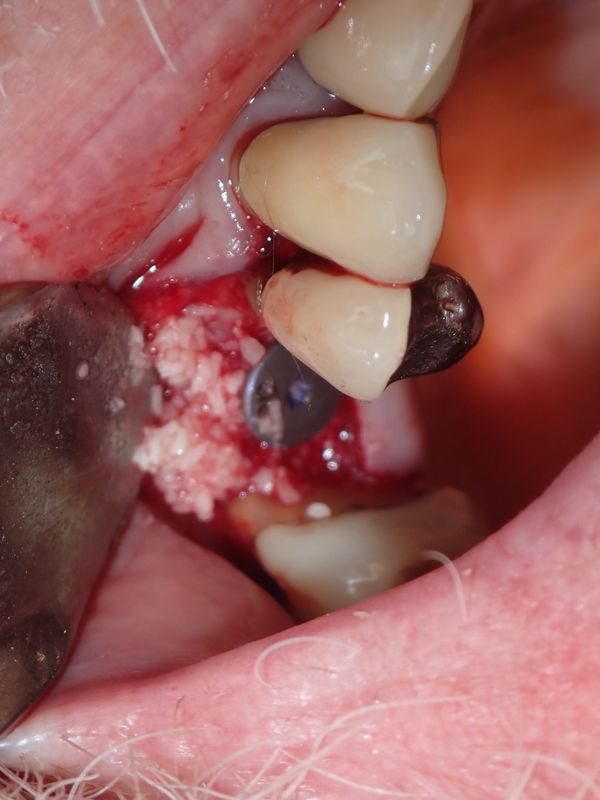

P9160019.JPG

Olympus TG-6

1/100s f/4.9 at 18.0mm iso200 full exif